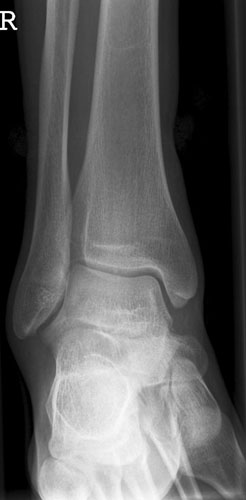

OSG seitlich

132_4.jpg

Fehler

Doppelkonturierung im oberen Teil der Talusrolle. Die Beurteilung des OSG ist nicht möglich. Die Spitze des Malleolus lateralis steht höher als die Spitze des inneren Malleolus.

Abhilfe

Der Fuß muss gesamthaft etwas höher gelagert werden, bei streng seitlicher Zentrierung.